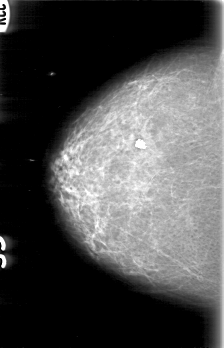

D_4089_1.RIGHT_CC

RIGHT_CC LINES 5206 PIXELS_PER_LINE 3346 BITS_PER_PIXEL 12 RESOLUTION 43.5 NON_OVERLAY